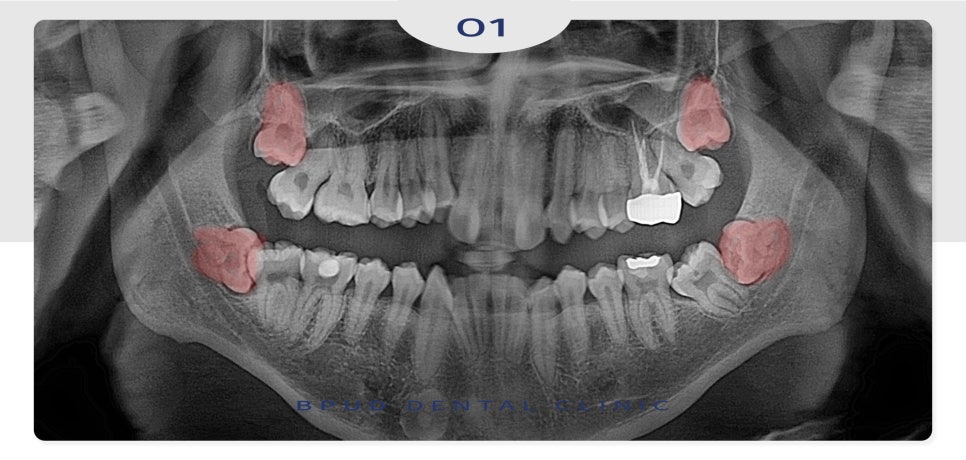

오늘은 양쪽에 매복되어 있는

사랑니 4개 모두 발치를 진행하신

부평동치과 환자분을

소개해 드리려고 합니다.

악궁이 작아서 치아 교정을 진행 중이신

상태로 사랑니 또한 완전히 매복되어 있었고

앞쪽 치아에 걸려 난이도가

매우 높은 케이스였는데요.